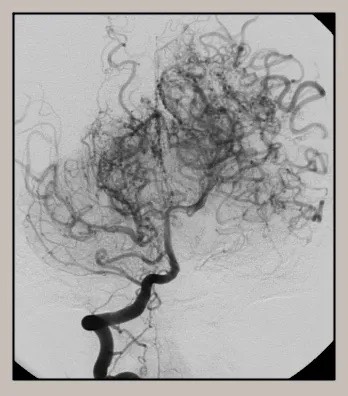

모야모야병은 뇌혈관, 특히 뇌로 혈액을 공급하는 내경동맥과 그 주변 주요 혈관이 점점 좁아지고 막히는 희귀 난치성 질환으로, 혈류가 줄어든 뇌는 부족한 혈액을 보충하기 위해 가느다란 미세측부혈관들을 새로 만들어냅니다. 이 작은 혈관들이 연기처럼 보인다고 하여 일본어로 ‘모야모야(안개·연기)’라는 이름이 붙었습니다. 소아부터 성인까지 폭넓게 나타나며, 특히 5~10세 어린이와 30대 전후의 여성에서 비교적 많이 발견되는 경향이 있습니다. 증상은 일시적 마비, 언어장애, 두통, 실신, 경련 등 매우 다양해 뇌졸중과 유사하거나 초기에는 가벼운 신경학적 증상으로만 나타나 진단이 늦어지기도 했습니다. 질환이 진행하면 허혈성 뇌졸중(뇌경색)이나 출혈성 뇌졸중 위험이 증가하여 반드시 전문적인 관리가 필요합니다. 아직 완전히 예방할 수 있는 방법은 없지만 조기 진단과 적절한 치료를 통해 뇌 기능을 보호하고 삶의 질을 유지할 수 있습니다.

모야모야병은 뇌기저부의 주요 혈관이 서서히 협착되고 막히면서 뇌혈류가 감소하는 만성 진행성 뇌혈관 질환입니다. 협착이 진행된 부위를 대신해 뇌는 생존을 위해 얇고 약한 혈관망을 만들어 혈류를 보충하려 하고, 이 새로운 혈관들이 촬영 영상에서 연기처럼 퍼져 보인다고 하여 ‘모야모야’라는 이름이 붙었습니다. 기전적으로는 내경동맥 말단부와 중대뇌동맥·전대뇌동맥의 기시부에 병변이 가장 잘 생기며, 시간이 지남에 따라 양쪽에 대칭적으로 나타나는 특징을 보였습니다. 이 질환은 단순한 혈관 협착이 아니라 진행성 변화이기 때문에 치료하지 않으면 혈류 부족이 심해지고 뇌 손상이 누적될 수 있습니다. 또한 뇌기능이 체력·호흡·체온 변화 등에 민감하게 반응하기 때문에 과호흡, 울음, 격렬한 운동, 감염 등으로 증상이 악화될 수 있습니다. 즉, 모야모야병은 시간이 지나면서 뇌혈류를 감소시키고 뇌졸중 위험을 높이는 질환이며, 평생 관리가 필요한 만성적 특성을 갖고 있습니다.

모야모야병의 핵심 치료는 뇌혈류 공급을 위한 새로운 통로를 만들어주는 수술입니다.

① 직접 우회술(Direct bypass)

• 측두동맥(STA)을 직접 뇌혈관(MCA)과 연결해 혈류를 즉시 공급하는 방식 • 성인에서 가장 많이 시행

• 수술 직후부터 혈류 개선 효과가 빠르게 나타납니다.

② 간접 우회술(Indirect bypass)

• 근육이나 막 조직을 뇌 표면에 붙여 그 조직에서 자라는 새로운 혈관이 뇌를 공급하도록 유도 • 소아에서 많이 사용

• 혈류 증가 효과가 나타나기까지 수개월이 필요합니다.

③ 혼합 우회술(Combined bypass)

• 직접 + 간접 방법을 동시에 시행하는 방식

• 빠른 효과 + 장기 안정성을 동시에 노릴 수 있는 방법입니다.